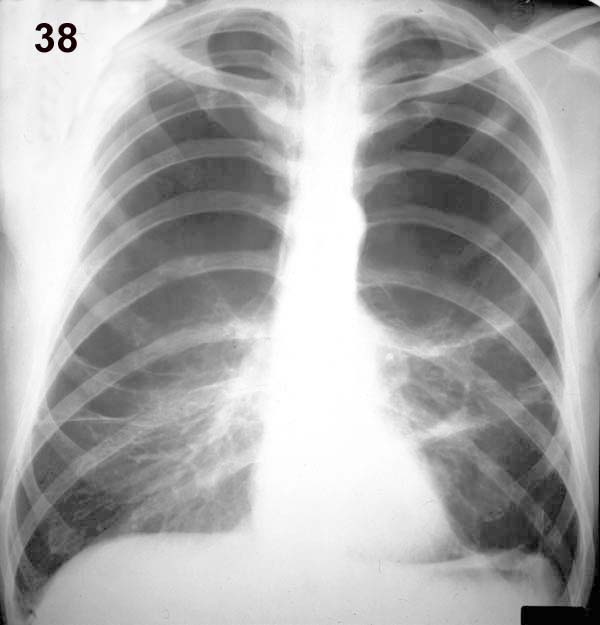

Placa 38